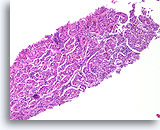

Lobulair carcinoom, Borst FNA, celblok.

Lobulaire carcinoomcellen lijken in het stromaweefsel te zijn ingebed, zodat de indruk wordt gewekt van hypercellulariteit. Dit kan de reden zijn waarom cytologische preparaten van een lobulair carcinoom vaak weinig maligne cellen tonen.

Lobulair carcinoom, Borst FNA, celblok.

Lobulaire carcinoomcellen lijken in het stromaweefsel te zijn ingebed, zodat de indruk wordt gewekt van hypercellulariteit. Dit kan de reden zijn waarom cytologische preparaten van een lobulair carcinoom vaak weinig maligne cellen tonen.

Lobulair carcinoom, Borst FNA, celblok.

Een enkele rij minimaal atypische spaarzame cellen die op en in de stromale fragmenten vastzitten, kan worden waargenomen. Let op de kenmerkende targetoïde intracytoplasmische vacuolen van lobulaire neoplasie.

Lobulair carcinoom, Borst FNA, celblok.

Een enkele rij minimaal atypische spaarzame cellen die op en in de stromale fragmenten vastzitten, kan worden waargenomen. Let op de kenmerkende targetoïde intracytoplasmische vacuolen van lobulaire neoplasie.